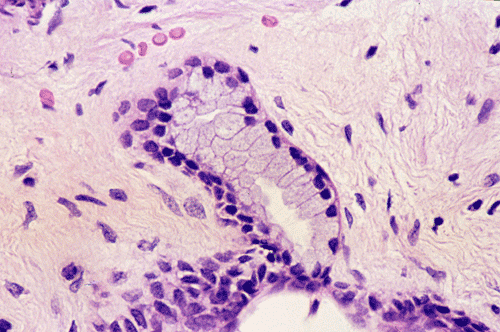

On low-magnification (Panel A),  the lesion contains has multiple glandular structures in a background of fibroconnective tissue. There is no inflammation. The epithelial component does not seem to have a complex architecture or papilla. On medium-magnification photographs (Panel B and C), the lining epithelium is low-columnar and single layered. Mucin secretion is noted on high-magnification photograph (Panel D). On intraoperative cytologic preparation (squash preparation), the single layer architecture of low-columnar cells is well appreciated (Panel E).